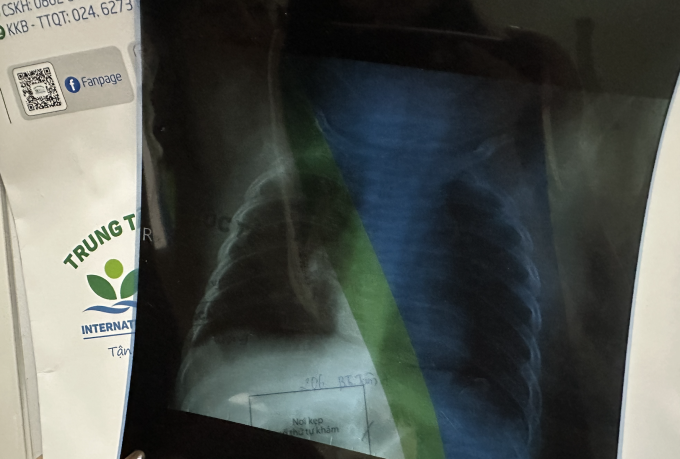

Xquang phổi của bé con chị Linh xác định viêm phổi nhẹ, kèm viêm tai giữa, ứ dịch, ho nhiều, buộc phải nhập viện. Ảnh: Nhân vật cung cấp